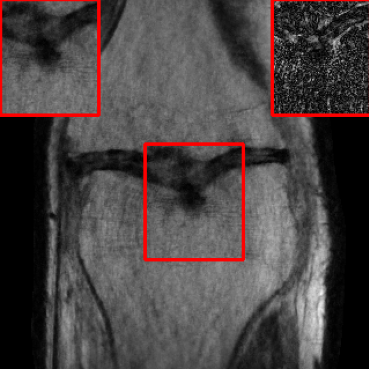

| Ground Truth | Initial | Global | LONDN-MRI | LONDN-MRI | Oracle |

![]() |

| PSNR = dB | PSNR = 19.41 dB | PSNR = 26.52 dB | PSNR = 27.76 dB | PSNR = 27.85 dB | PSNR = 27.92 dB |